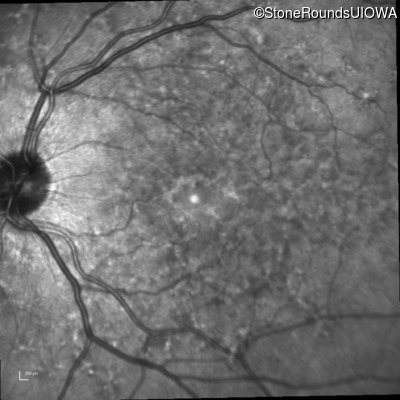

Infrared Fundus Photograph - Right - 20/20

Exemplar